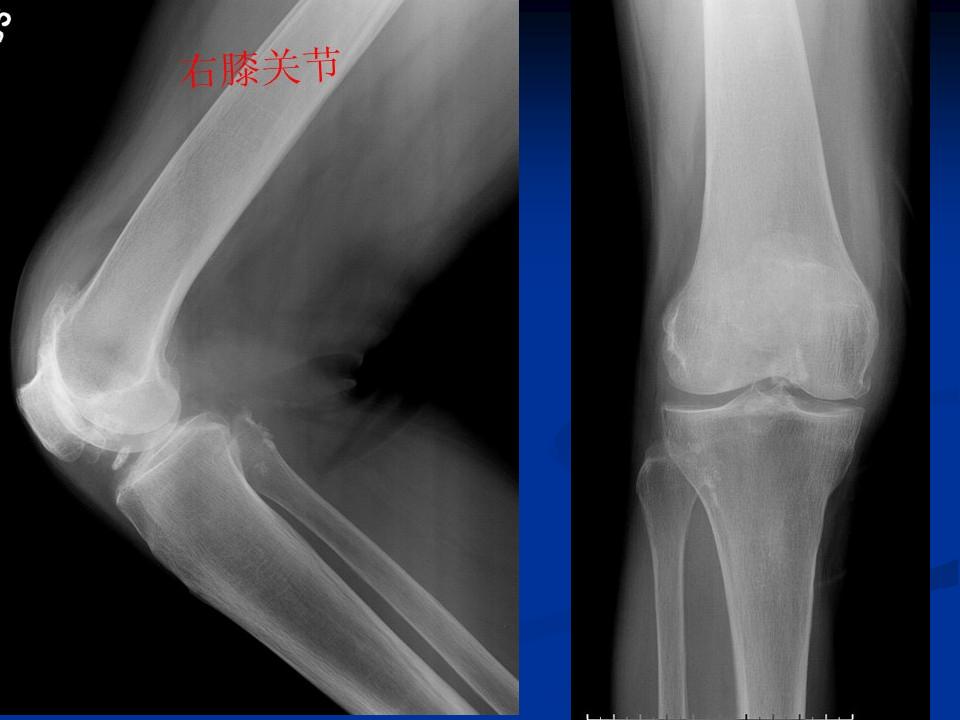

影像学检查 X线 四个方向X线影像 l 早期可无改变 l关节间隙变窄、不均匀、消失(成人<3mm; 老年人<2mm)。 l骨赘形成 l关节内游离体、骨质疏松 l软骨下骨板硬化、囊性变